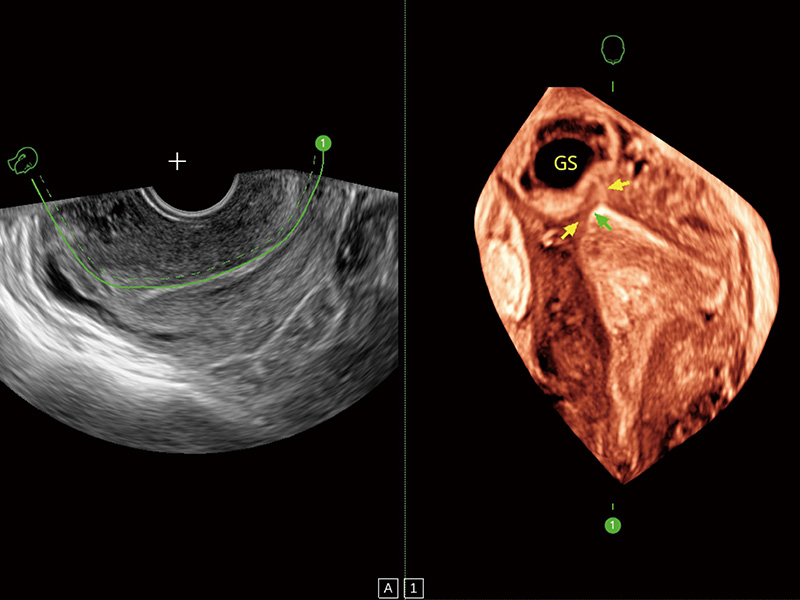

腔内容积探头

腔内三维成像技术获得显著提升,超大扇角在满足日常基础扫查的同时,支持卵泡自动测量及多种三维渲染模式,为您提供更多的诊断信息,尤其是在子宫畸形的诊断,内膜及肿瘤占位观测中起到了重要的作用。

中央型宫腔粘连

子宫内膜息肉